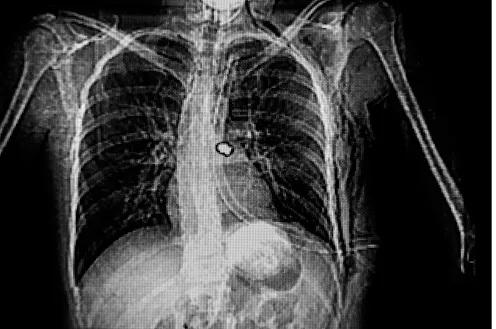

Medical radiography was still in its infancy. The German physicist Wilhelm Conrad Röntgen had discovered X-rays in 1895, and the following year created the first X-ray photograph, memorably revealing the bones of his wife’s hand. Two decades later, suitable machines were available in major hospitals, but they were located too far away to help soldiers injured on the battle field.

Curie won two Nobel Prizes for her pioneering research into radioactivity, but during the war she abandoned her laboratory to support her adopted country. Her Curie cars brought radiography equipment – including miniature dark rooms for developing prints – right to the scene of battle, so that soldiers could be examined and treated immediately.

In a letter to Davidson, Gleichen explained that they needed to work quickly. With more and more wounded soldiers arriving daily, many of them already close to death, there was often no time for the luxury of standard procedures. Weighing down their un-anaesthetised patients with sandbags, they explored precisely yet rapidly to locate bullets lodged in a soldier’s body by a rough-and-ready technique of aiming along two perpendicular lines to see where they intersected.

Gleichen was particularly jubilant about managing to pinpoint a bullet deep inside a soldier’s skull. She sent Davidson a small sketch, telling him that she was “cocka hoopy”. Despite this experimental success, she faced up to wartime realities: “Anyway it has been deeply interesting + I expect they will kill him by operating + equally kill him by leaving it. I am sorry as he was such a nice boy in tremendous spirits + health.”